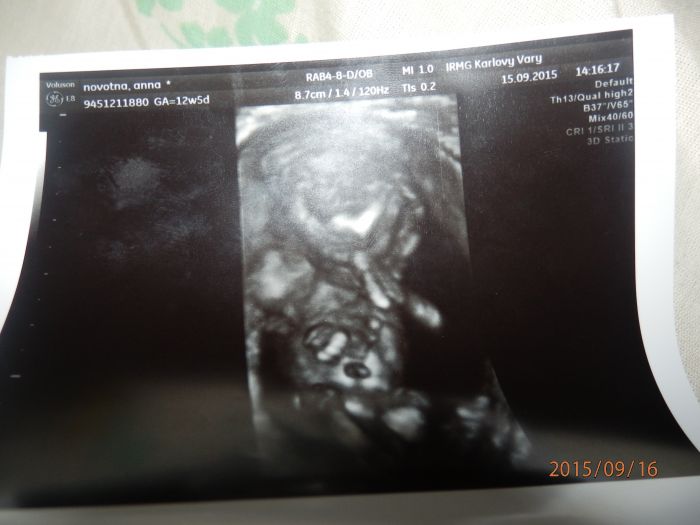

Ahojky maminky, těhulky tak se sem přidávám podle poslední ms mám termín porodu 24.března je to mé 3 těhotenství druhé nedopadlo :-/. Mám doma 26 měsíční holčičku a ted na 70-80% čekám kluka již 4 večer cítím pohyby slaboučké ale krásné. Toto těhu bylo náročné hlavně na bolesti břicha a nevolnosti ale vše už pomalu ustupuje :-) přikládám foto z ultrazvuku a foto 2 leté dcerky Aničky :-)